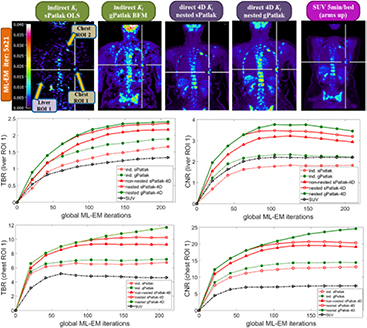

These observations were further supported by the TBR and CNR quantitative analysis on the same four Ki image ROIs in figure 6. Nevertheless, it should be noted that 4D imaging methods were associated with a relatively higher gain in CNR rather than TBR scores, as the main benefit of direct over indirect parametric reconstruction is the reduction of the noise in the Ki images. The TBR relative enhancements of 4D over indirect algorithms can be attributed to the reduction of noise-induced bias for the former, as also indicated by the noise-bias trade-off analysis in figure 5(c). Nevertheless, the ground true TBR Ki contrast, as calculated from the true input values of our simulation study, was underestimated in all cases. In all cases, the observed bias in the lesion Ki estimates and respective underestimated TBR scores becomes higher for smaller diameters (A2 and B2 ROIs), which we attribute to the partial volume effects.

Figure 6. TBR (1st column) and CNR (2nd column) quantitative analysis for A1, A2, B1 and B2 target ROIs on simulated Ki parametric images for a range of indirect and direct (s/g)Patlak methods. The same number of nested Patlak ML-EM sub-iterations and gPatlak-4D initialization scheme are employed, as for figure 5. TBR and CNR scores were averaged over 20 noise realizations with the standard deviation illustrated with error bars.

In figure 8, we present a set of indirect and direct (s/g)Patlak Ki WB images from a patient dataset at a 10–45 min p.i. scan time window. Moreover, the respective SUV WB PET image is also shown, as acquired at 60 min p.i. with the standard-of-care static PET protocol. The directly reconstructed (s/g)Patlak WB Ki images were estimated after five cycles of 21 ML-EM global iterations each. A nested 4D ML-EM implementation was employed at each bed position involving 20 sub-iterations. Furthermore, the first 3 out of the 5 ML-EM iteration cycles of the gPatlak 4D WB reconstruction consisted of sPatlak 4 D ML-EM iterations to initialize the 4th cycle of gPatlak ML-EM iterations (figure 9).

Figure 8. (1st row): clinical WB (s/g)Patlak Ki images, as estimated either indirectly or directly from the raw dynamic (10–45 min p.i) 18F-FDG PET data with 4D and indirect methods with patient arms at the bottom position to withstand longer scan duration. Also, the respective static SUV image obtained at 60 min p.i., after repositioning same patient with arms in the standard upper position (2nd and 3rd rows): TBR and CNR scores versus iterations for a range of (s/g)Patlak and SUV methods from a chest and a liver suspected tumor lesion ROIs.

The spatial noise levels visually observed in the background regions of the selected liver and chest target ROIs of WB 4D (s/g)Patlak Ki clinical images of figure 8 were comparable to the respective static SUV image noise. This is also evident by comparing the TBR and CNR scores of respective clinical Ki and SUV images for both evaluated ROIs in the same figure. In particular, the superiority of Ki imaging, relative to SUV, in terms of TBR contrast is also retained to nearly the same or higher degree in terms of CNR score. As CNR is derived from TBR after normalizing the latter with spatial noise in the target background, the previous observation suggest similar or lower quantitative levels of spatial noise between direct 4D Ki and SUV clinical images, at least for the two evaluated ROIs. Thus, our results demonstrate the clinical feasibility of 4D WB Patlak Ki methods, when applied on a streamlined 6-pass WB PET protocol. In addition, the superior TBR and CNR 4D Ki scores, relative to SUV, on the two identified ROIs indicate potential enhancement of tumor detectability performance, when complementing the currently established in clinic WB SUV imaging protocols with the proposed direct 4 D WB (s/g)Patlak methods.

3.2.2. Direct 4D versus indirect Patlak WB clinical imaging.

The images in figure 8 illustrated the lower noise of direct 4D relative to indirect Patlak methods. Moreover, the quantitative plots in figure 8 demonstrated the superior TBR and CNR performance for all 4D Patlak methods, compared to the respective indirect methods, particularly for the chest ROI. The improvement was more evident in terms of the CNR metric, owing to the lower noise levels observed in the 4D reconstructions versus indirect Patlak analysis. Our clinical findings confirmed the simulation results and can be explained by the more efficient utilization of the acquired data with 4D Patlak algorithms. Finally, the quantitative TBR and CNR analysis suggested that the gain observed when switching from indirect to direct 4D Patlak methods is relatively larger than the respective gain between standard and generalized Patlak models.

3.2.3. sPatlak versus gPatlak 4D WB clinical imaging.

Our clinical validation results in figure 8 demonstrated the superior TBR lesion contrast scores for nested gPatlak 4D Ki images, both via the qualitative inspection of the respective patient WB Ki images as well as through the quantitative TBR analysis in both evaluated ROIs. Moreover, despite the higher noise levels observed in gPatlak Ki images, relative to sPatlak, the highest clinical ROI CNR scores were systematically observed for the former. Besides, the clinical TBR and CNR score differences between the two 4D Patlak methods were not as significant as the respective differences between (i) indirect sPatlak and gPatlak or (ii) direct versus indirect Patlak methods. In other words, the differences between the two Patlak models were less significant in the 4D framework.